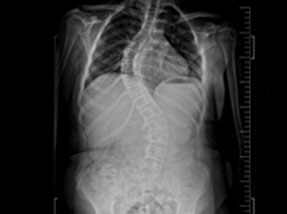

• Pre-Surgery

• Pre-SurgeryBefore

Case 1